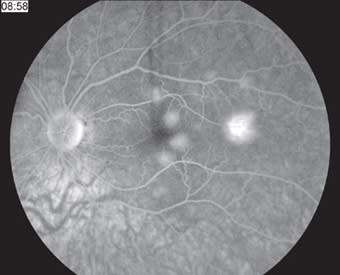

In 1968, Gass first described this self-limited inflammatory condition, acute posterior multifocal placoid pigment epitheliopathy (APMPPE), in which multiple white-yellow placoid lesions develop at the level of the retinal pigment epithelium and cause a rapid reduction of central vision in otherwise healthy young adults. The yellow-white retinal lesions fade to patches of RPE atrophy and hypertrophy, though all phases may be observed simultaneously. The visual changes typically recover within three weeks, though recovery may be limited with foveal involvement. Characteristic early hypofluorescence and late hyperfluorescence on fluorescein angiography (Figures 7 and 8) may be related to choroidal ischemia and a resultant delay in filling. Given an association with HLA-B7 and HLA-DR2, an immune-mediated mechanism and genetic susceptibility have been proposed. RP

Figure 7. At presentation, early-phase fluorescein angiogram showing initial hypofluorescence of RPE lesions.